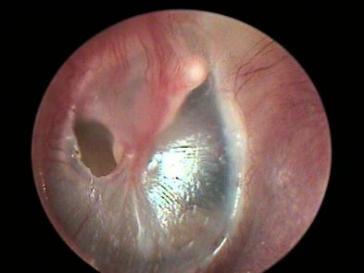

鼓膜又称耳膜 , 属于中耳的一部分 , 是椭圆形半透明状薄膜 , 大小约9*8mm , 由上皮层、纤维层和黏膜层构成 。

鼓膜穿孔是门诊常见的疾病 , 可导致听力下降和中耳反复感染 。 鼓膜穿孔不能自愈的话常常需要修补 , 鼓膜修补术是耳显微外科最基本的手术 。

鼓膜穿孔根据部位分为紧张部穿孔和松弛部穿孔 , 根据穿孔大小又分为大、中、小穿孔 。